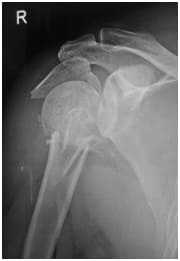

Very bad fracture with Many parts

intra operative picture